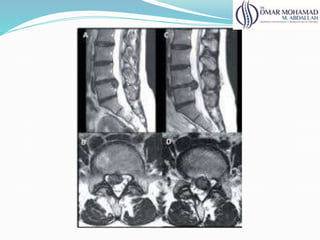

Rnm

● Melhor avaliação do disco e estruturas neurais;

● 100% de alt acima de 50 anos (lombar)

● 60% de alt acima de 60 anos (cervical)

● Correlacionar os achados com clínica

● Avalia: estabilidade, compressão e deformidades

61

Rnm ● Melhor avaliaçãodo disco e estruturas neurais; ● 100% de alt acima de 50 anos (lombar) ● 60% de alt acima de 60 anos (cervical) ● Correlacionar os achados com clínica ● Avalia: estabilidade, compressão e deformidades 61